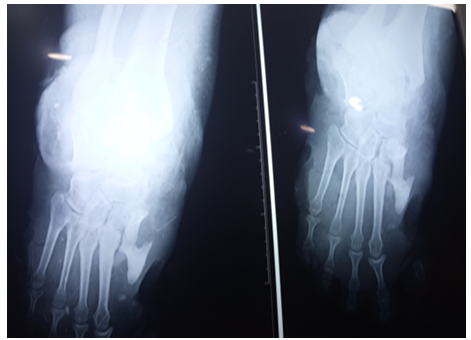

Figure 3. X-ray showing osteitis

The electromyogramme showed a sensory peripheral neuropathy. Cubic deformity of the left foot and osteitis were observed in X-ray of the foot [5]. At the end of his explorations no specific pathology was detected to explain these torpid lesions. The diagnosis of acrodystrophic neuropathy linked to TD was established based on the distal peripheral sensory neurogenic syndrome and the result of the electromyogram and after exclusion in the others etiologies (diabetes, Charcot-Marie-Tooth disease, Bureau and Barriere’s Disease linked to alcoolic intoxication, amyloidosis...) [6,7]. The treatment was limited to local care, bandages, immobilization and antibiotic therapy. Despite the local care and the appropriate broad-spectrum antibiotic therapy, and dump shoes we deplored a torpid progression of the lesions resulted in osteitis and warranted elective amputation of right mid-leg (Figure 1, 2 and 3) [7].